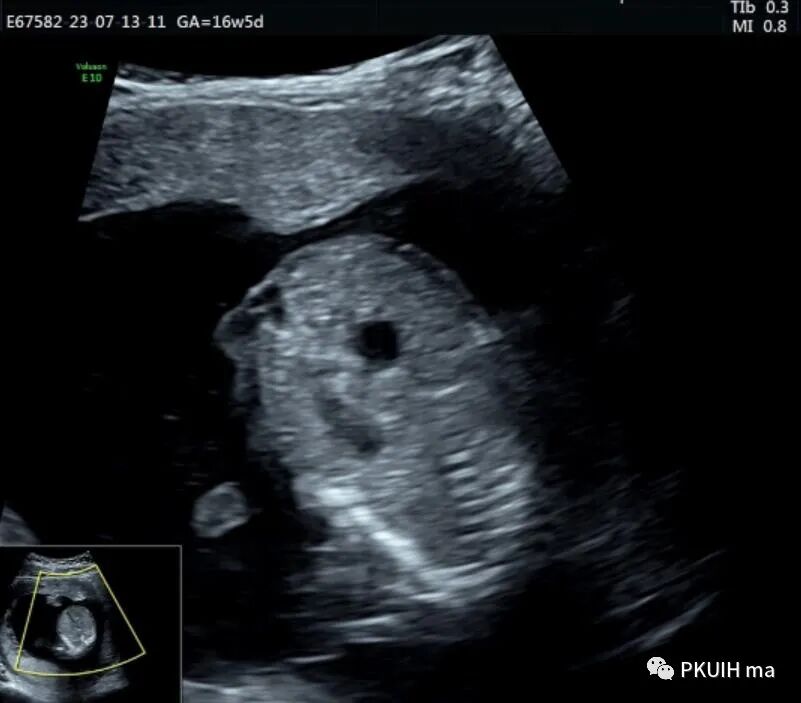

胎儿中腹部见一囊性包块,大小约1.2x1.0x0.8cm,边界清,形态规则,内透声好。囊肿位于脊柱前方、胆囊后方、门静脉窦旁,与后肾接近

观察囊肿与肾、胃泡、膀胱均无相关。

仔细观察囊肿壁好像不完整,周边见微小管道回声与囊肿相通

本病可于中孕及晚孕期被发现,其超声特征为肝门区囊性包块,形状呈圆形或椭圆形,位于门静脉右前方,可对门脉造成压迫。如果显示囊性包块与胆囊相通,则有助于诊断,彩超一般内部无血流信号。